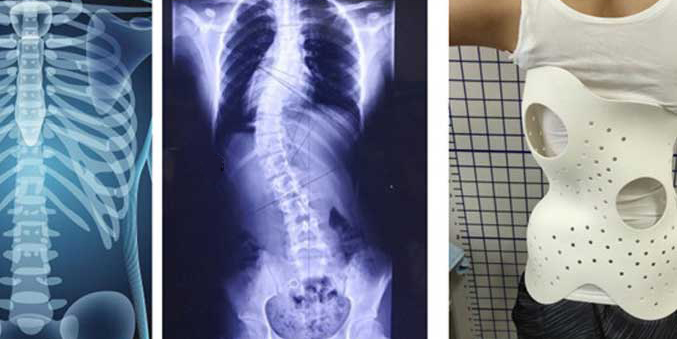

According to studies, at least 2%-3% of people have scoliosis (one/both sides). Most people can be diagnosed before age 7 and can be cured with the right treatment. At various stages of treatment, there is something beneficial for all scoliosis sufferers, such as a dorsal brace. It aids in spinal correction procedures and speeds up treatment.

However, the existing braces have problems such as poor air permeability, the design cannot fully fit the patient's body, the wall thickness of the device, and the unsightly style, etc. These problems make the patient's wearing compliance poor, thereby affecting the treatment effect.

Medical institutions and rehabilitation aids manufacturers at home and abroad have begun to manufacture more lightweight and beautiful customized scoliosis orthoses through 3D printing technology.

Recently, Dr. Kevin Lau from Singapore designed a spinal brace, which was made by printing TPU78D on the Mingda MD-600 Pro large-size 3D printer. It was perfectly customized according to the user's body structure, and the 3D printed product was perfectly fitted and perfectly supported. The clothes are also light and comfortable on the outside, and 3D printing helps improve the patient's condition in the most comfortable way possible.